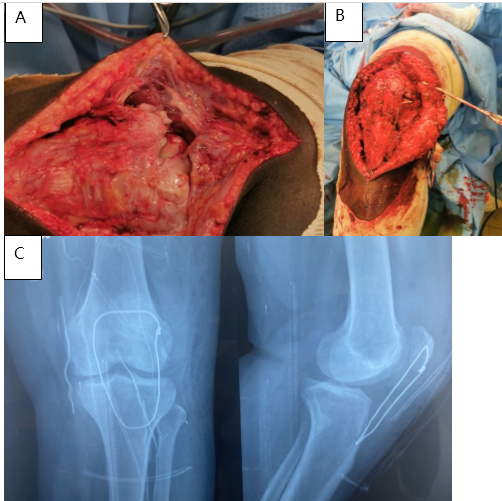

Surgery was performed under spinal anesthesia with the patient supine. A medial parapatellar approach revealed rupture of the tendon 1 cm distal to the patellar insertion with frayed edges. Tendon repair was performed and reinforced with a protective steel wire frame (Fig. 2).

Figure 2: Intraoperative view of the patellar tendon rupture (a), tendon repair (b), and post-operative control radiograph (c) – Patient 1.

Rehabilitation was initiated 6 weeks postoperatively. At 8-month follow-up, the patient had regained full active knee extension.